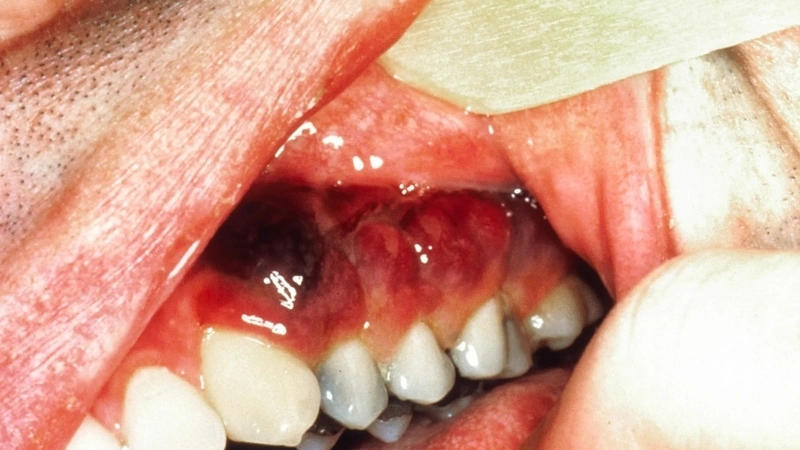

Image description of Kaposi's Sarcoma

Kaposi's Sarcoma is a rare cancer caused by human herpesvirus 8, primarily affecting skin, lymph nodes, and internal organs. It often presents as purplish lesions or swelling and is more common in individuals with weakened immune systems.

- Purplish, red, or brown patches on the skin are the most common visible symptom of Kaposi's Sarcoma, often appearing on the legs or face.